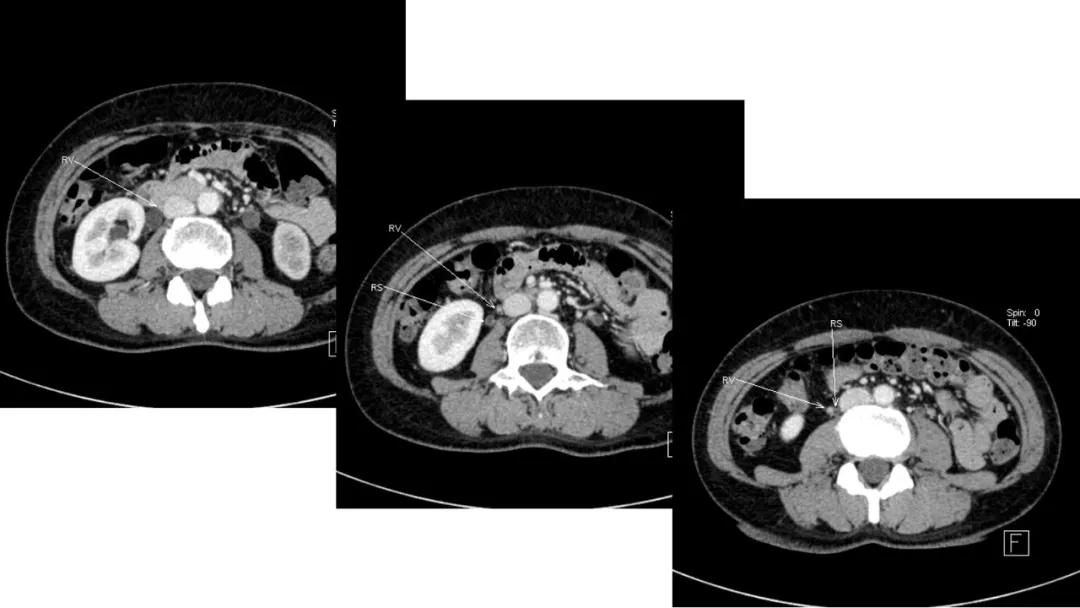

- 残存卵泡、卵巢动脉供血等征象往往有助于肿瘤定位

病例10

女,39 岁,体检发现盆腔肿块1月余

CA125:51U/ml

病理:左侧卵巢卵泡膜-纤维瘤